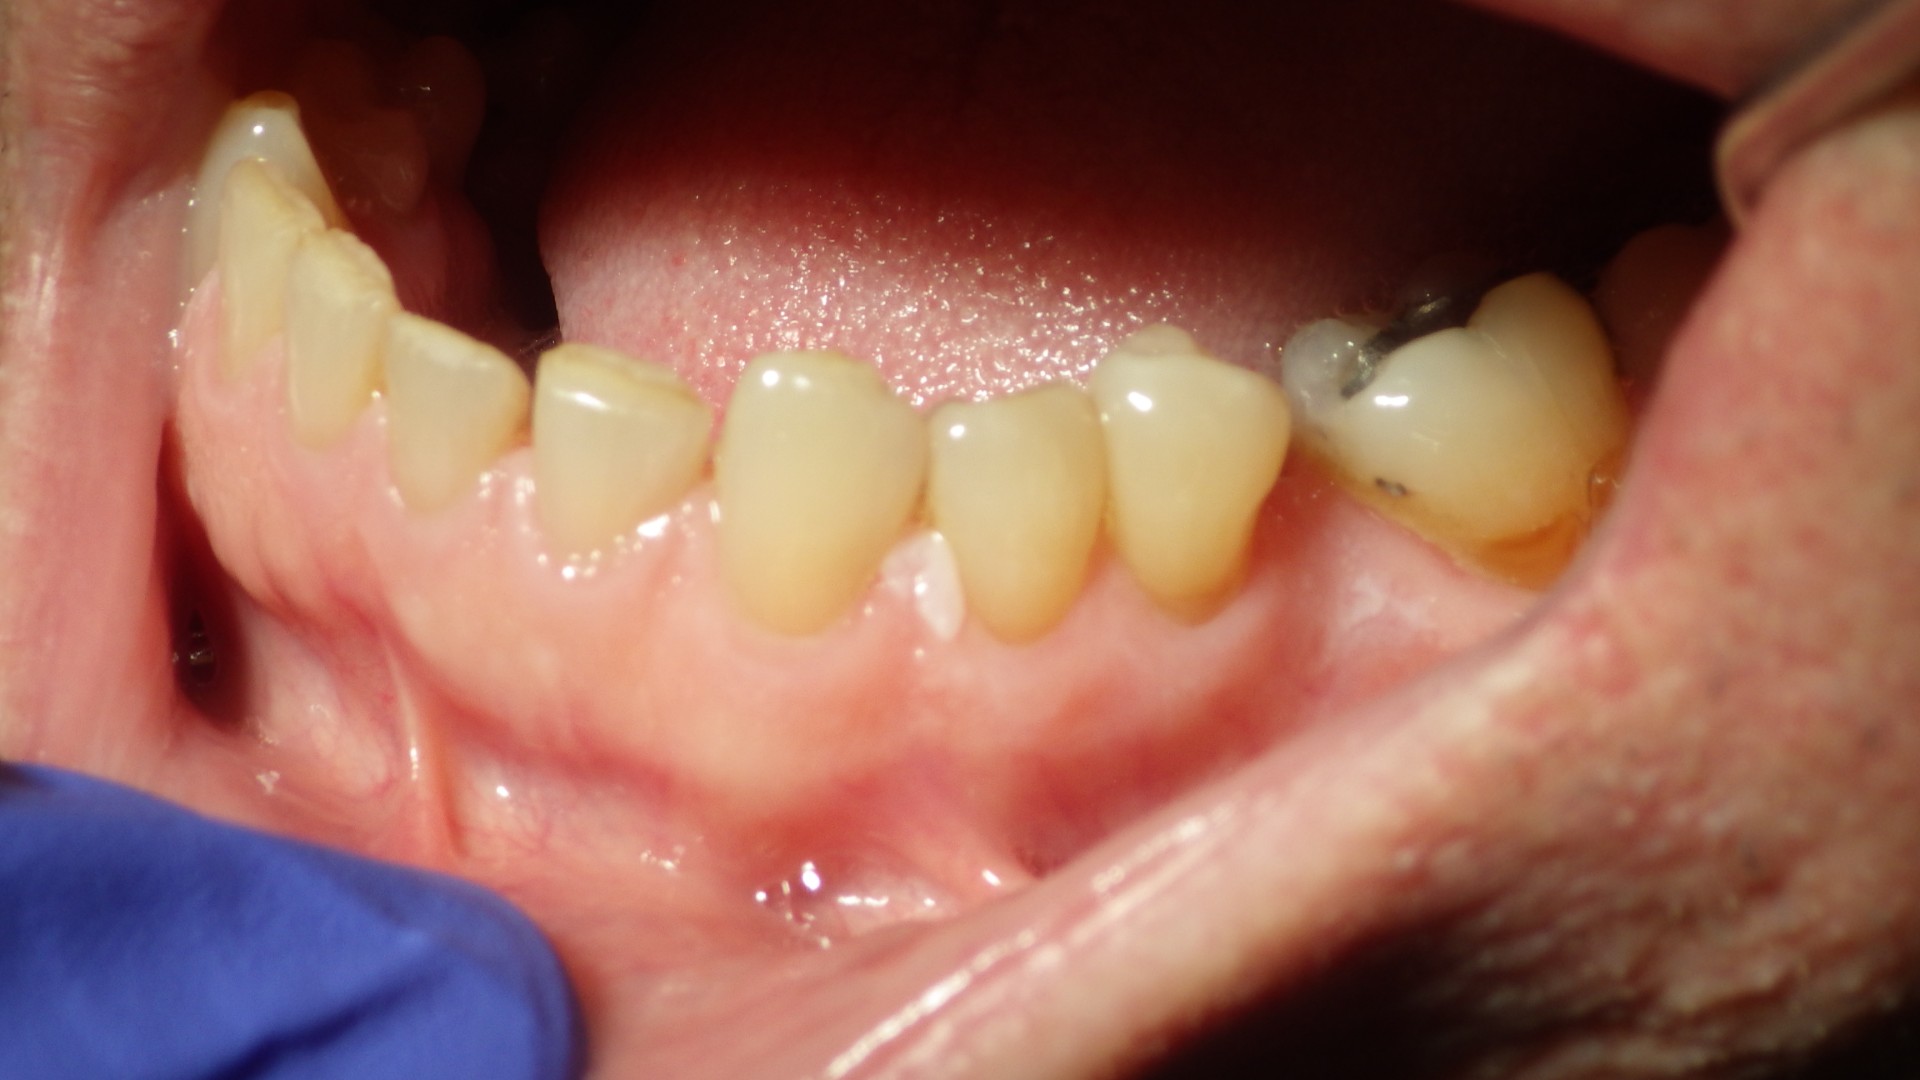

Figure 4. Focal keratotic white plaque involving the interdental papilla of the mandibular gingiva (attached gingiva). Clinical impression: leukoplakia.